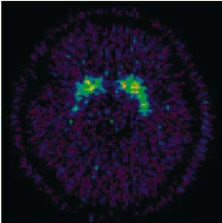

![]() |

The 11C-raclopride binding potential images at the level of the striatum for one participant during meditation (above) and during the speech (below). 11C-raclopride binding potential in ventral striatum is evidence of increase endogenous dopamine release during meditation.

According to the results, there was a significant decrease (7.9%) in BP in the ventral striatum. During active meditation, the participants reported a significant decrease in their readiness for action (p<0.05) along with heightened sensory imagery (p<0.05).

"The major finding of the present study has been the demonstration of increased dopaminergic tone in the ventral striatum during an altered conscious state...the fact that the ventral striatum was the only region in which the decrease in dopamine receptor availability reached statistical significance is of interest. Two of the three front-subcortical circuits regulating behavior include structures in the ventral striatum," the authors explained.